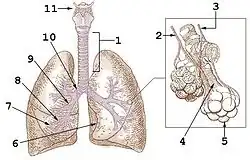

Cisuras y lóbulos

El pulmón derecho está dividido por dos cisuras (mayor y menor) en 3 partes o lóbulos (superior, medio e inferior). El pulmón izquierdo tiene dos lóbulos (superior e inferior) separados por una cisura (oblicua). La cisura mayor de ambos pulmones va desde el cuarto espacio intercostal posterior hasta el tercio anterior del hemidiafragma correspondiente. En el pulmón derecho separa los lóbulos superior y medio del lóbulo inferior, mientras que en el pulmón izquierdo separa los dos únicos lóbulos: superior e inferior. La cisura menor separa los lóbulos superior y medio del pulmón derecho y va desde la pared anterior del tórax hasta la cisura mayor. Puede estar ausente o incompleta en hasta un 25 % de las personas.

En cada lóbulo se distinguen diferentes segmentos, bien diferenciados, correspondiéndole a cada uno un bronquio segmentario (3.ª generación bronquial). Existen varias clasificaciones para nombrar a los diferentes segmentos, siendo una de las más aceptadas la de Boyden.[2] Los bronquios segmentarios se subdividen en bronquios propiamente dichos y bronquiolos (generaciones 12-16). Estos últimos carecen de cartílago y se ramifican en bronquiolos terminales y bronquiolos respiratorios (generaciones 17 a 19) que desembocan en los alvéolos: las unidades funcionantes de intercambio gaseoso del pulmón.